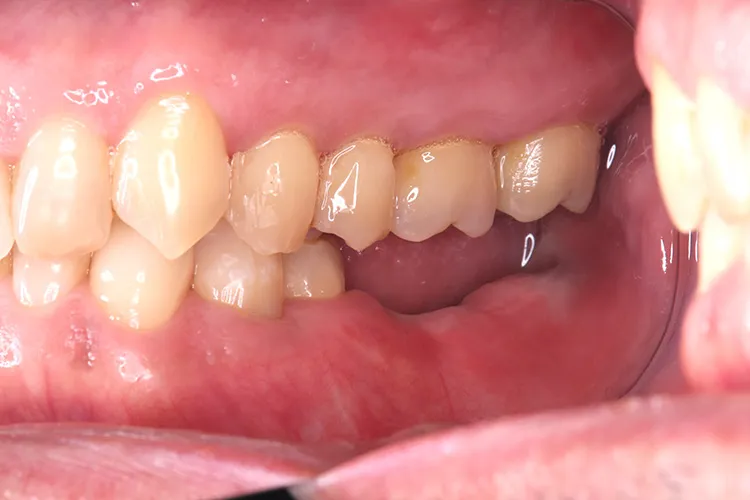

治療前

治療後

症例2/

臼歯1本

- 治療期間

- 3ヶ月

- 費用

- 51万円(税込)

治療内容

第一大臼歯1歯欠損をインプラントで回復したケースです。第一大臼歯は永久歯の中で一番最初に生える歯ですが、一番早く傷んでしまう歯でもあります。噛む力の60%を負担し噛み合わせの安定に大きく影響しますので、この歯が欠損すると噛み合わせに悪い影響を与えてしまいます。インプラントで治すことにより噛み合わせが安定するだけでなく、ブリッジのように隣在歯を削らないので天然歯の寿命を延ばすメリットもあります。